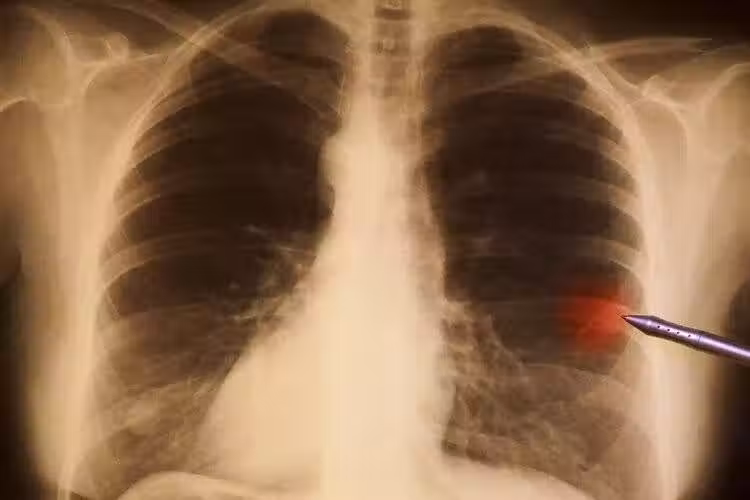

全球一年1929萬人患癌!四大惡性腫瘤「一發現即晚期」 再次提醒:這4種食物「再愛吃也要忌口 」

作為我國的第二大癌症,胃癌的發病數和死亡數不容樂觀。數據顯示,2018年我國每年胃癌新發67.9萬例,死亡49.8萬,約佔全球的50%,其中約90%的患者在確診時已是晚期。

胃癌晚期,意味著治療費用更高、治療效果更差、5年生存率更低,給個人和家庭帶來沉重的負擔。

想要提升胃癌的生存率,就要及時抓住癥狀,比如:上腹不適,尤其是餐後腹部飽脹、胸後部疼痛、胃部反流等;大便呈柏油色、黑色;短時間內體重大幅度下降。這些癥狀可能與胃癌有關,應及時檢查。